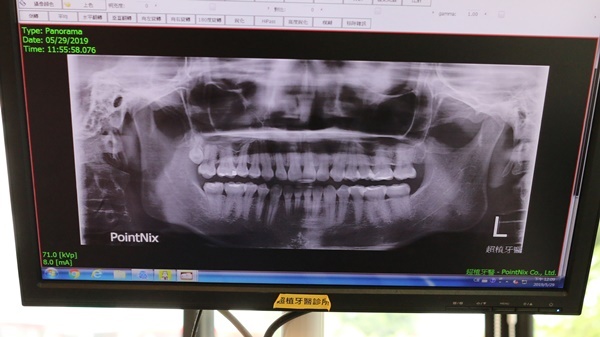

隨著醫療技術進步植牙雖然可以減少齒槽骨吸收、咬合力也幾乎可恢復至原有牙齒的水準,患者也可以不用磨掉旁邊鄰近的健康牙,選擇植牙方式來解決缺牙問題,植牙前專科醫師也必須要考量患者的狀況,例如齒槽骨高度、寬度、牙肉的狀況。

超植牙醫陳奕安醫師提出倘若患有糖尿病、心臟疾病、高血壓且控制不佳、長期使用抗凝血劑者、癮君子族群、癌症患者、骨質疏鬆者及血液或腎臟疾病患者,都是植牙的高危險群,植牙前都須特別注意並如實告知牙醫師自身健康狀況以降低植牙失敗問題發生。